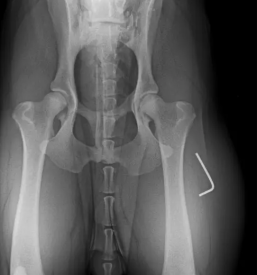

Vlagamo v najsodobnejšo diagnostično opremo (digitalni rentgen, UZ, krvni analizator...) in opremo za kirurgijo, da na enem mestu ponudimo celovito obravnavo na visokem nivoju.